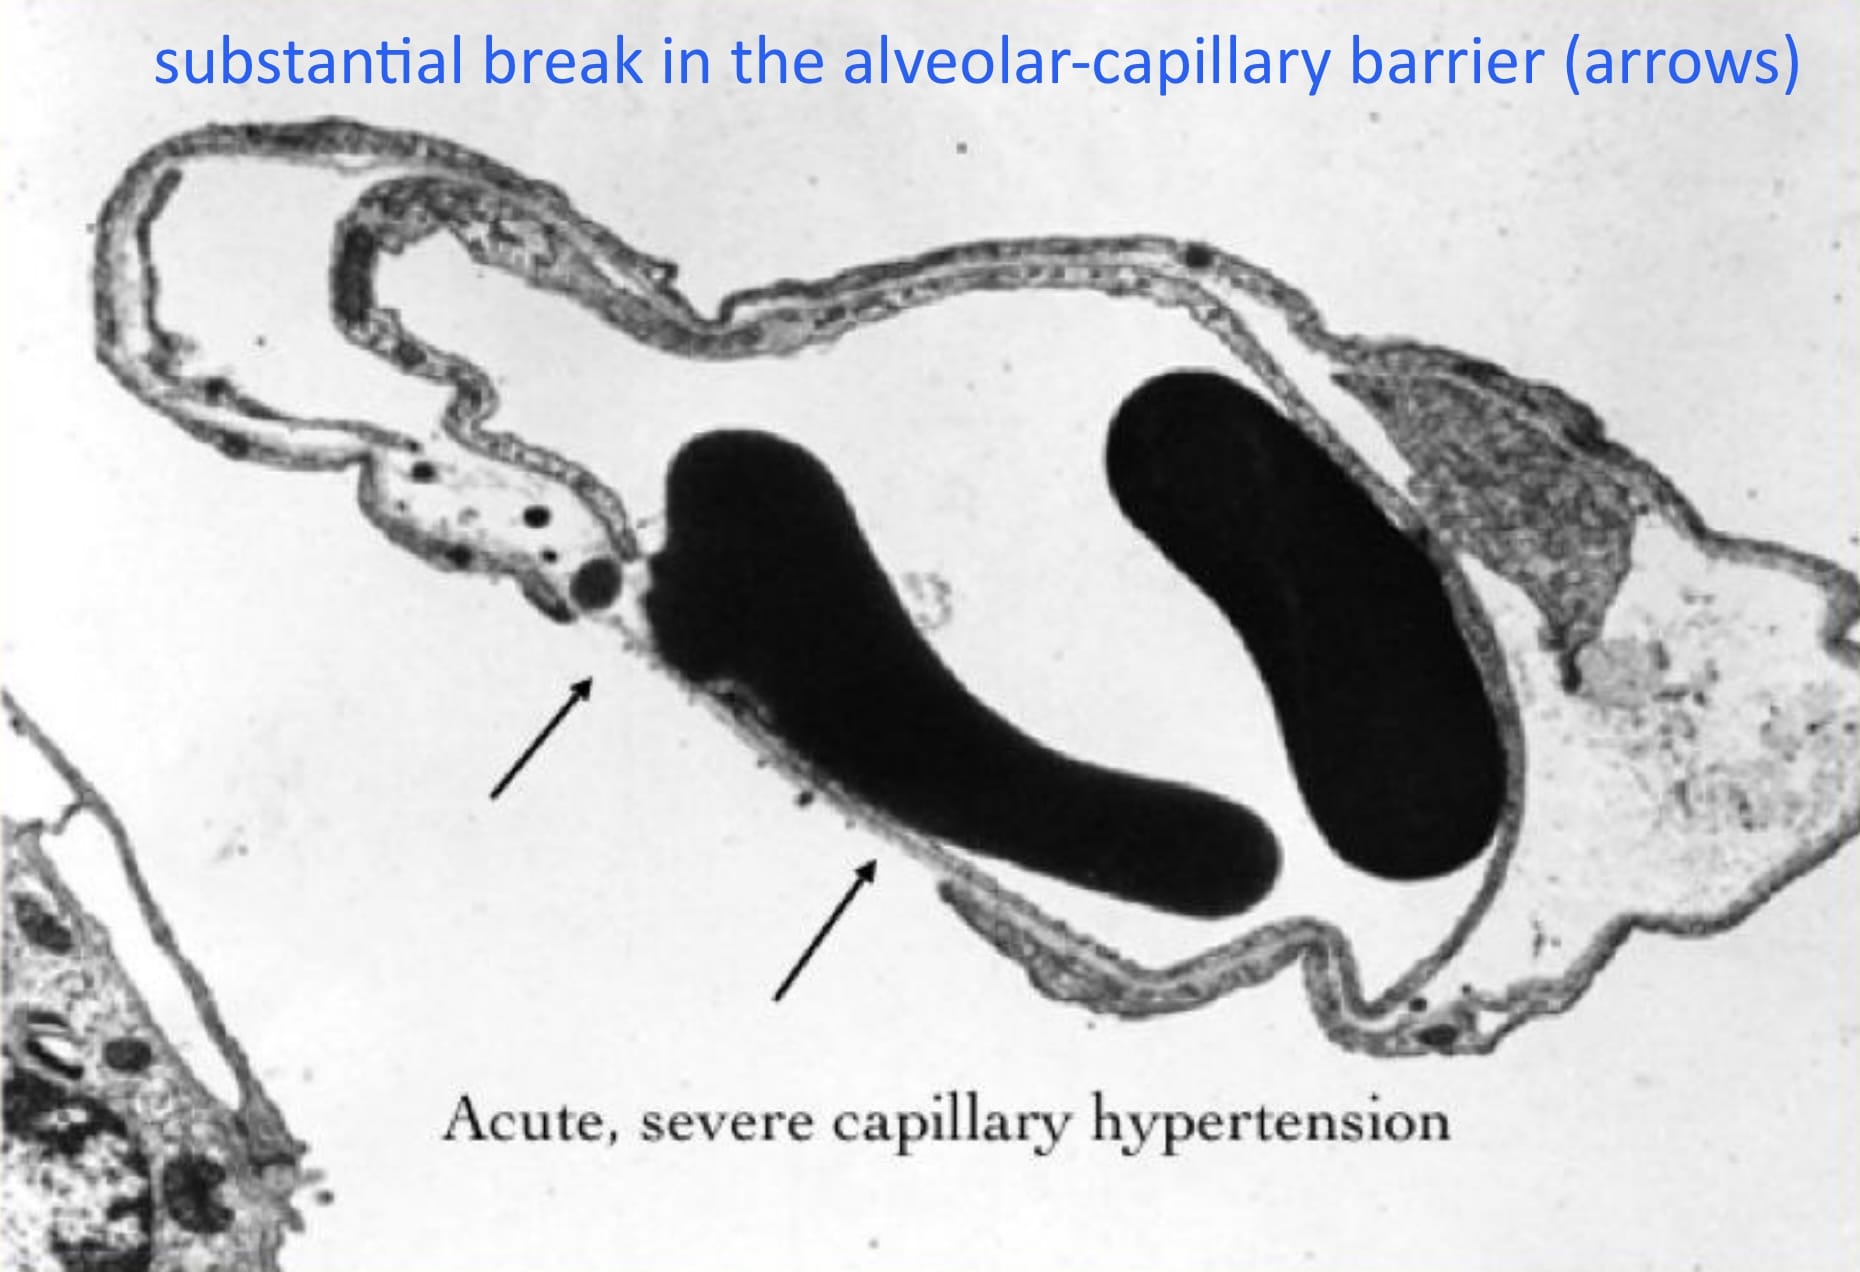

The explanation for these cases derives from the phenomenon of Stress Failure of Pulmonary Capillaries, a form of acute lung injury, involving the alveolar-capillary barrier. This was elucidated by John West – initially in the case of acute fatal lung edema in racehorses – and is nicely depicted in this figure from one of his articles.

• When hydrostatic edema is the result of acute and severe capillary hypertension, stress failure of the capillaries will disrupt this sequence.